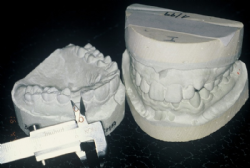

Erstellen von Kiefermodellen

Nach Abformung von Ober- und Unterkiefer und Feststellen der Bisslage werden Zahnmodelle aus Hartgips hergestellt. Diese werden analysiert und vermessen (Symmetrievergleich, Zahnformen, Platzberechnung usw.), wodurch das genaue Ausmaß der Fehlstellung festgestellt werden kann.